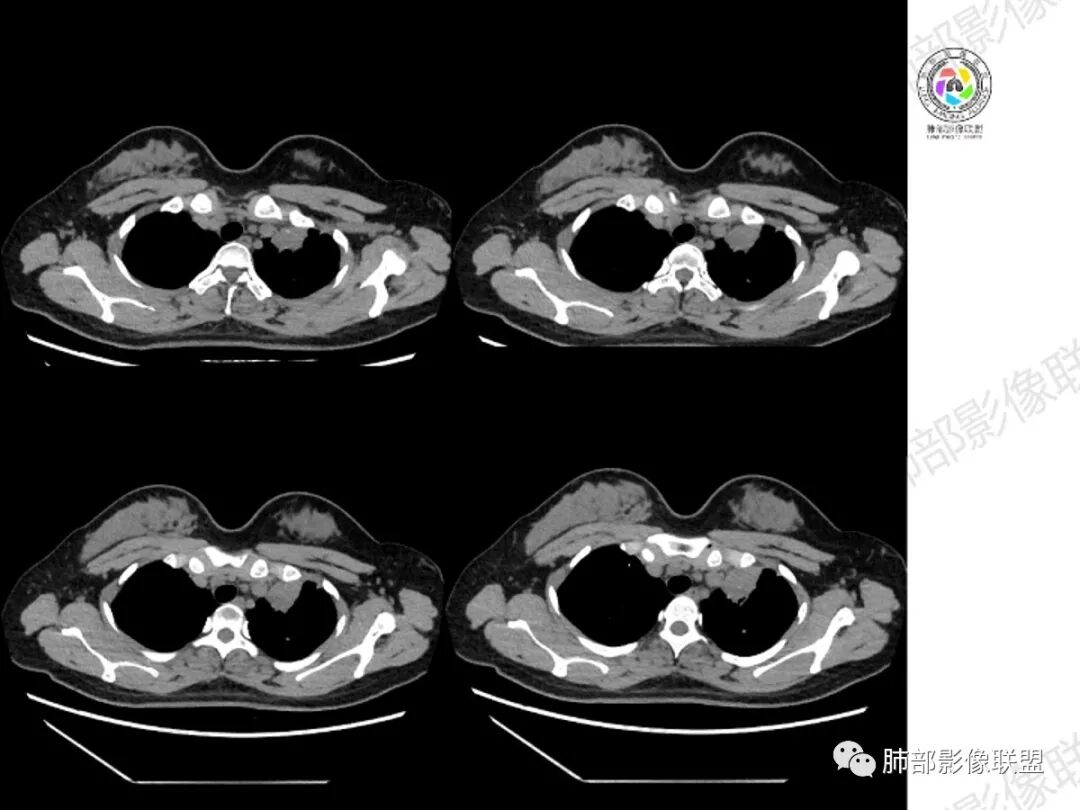

年轻女性,咳嗽咳痰一个月,左肺体积缩小,左肺尖部胸膜下实变影,宽基底与胸膜相贴,病灶边缘平直收缩,部分略膨隆,病灶下方可见支气管挤压,肺窗所示:周围伴有多发结节部分可见树丫征,纵隔窗可见病灶与纵隔胸膜黏连,部分与左肺动脉分界欠清,平扫密度尚均匀,增强扫描不均匀强化,内部可见多个低密度坏死,伴有条状血管影,纵隔淋巴结略有肿大。

胸部CT:左肺体积缩小,左肺上叶前段纵隔旁胸膜下大片实变影,边缘清楚、匀齐、平直收缩,部分略膨隆,周围多发结节、树芽卫星灶,纵隔窗病灶与纵隔胸膜黏连,实变内多发点状钙化。平扫密度尚均匀,增强扫描不均匀明显强化,多个低密度区,呈仙人掌样,伴有条状血管影,考虑慢性炎症伴左上叶前段支气管闭塞,TB?鉴别黏表、腺癌等。

青年女性、痰血症状一月,左胸廓缩小,左上肺固有段支气管狭窄堵塞,前段支气管扩张伴粘液栓、远侧肺不张,肿块整体呈梭形沿前段支气管爬行向外延伸,内可见多处圆形低密度坏死灶,肺不张处血管造影强化明显,周围散发束状细小结节灶,肺门及纵隔淋巴结尚正常。考虑结核可能大。

1.纵隔明显左移,提示病灶存在时间较长,存在明显牵拉和/或肺不张的可能。